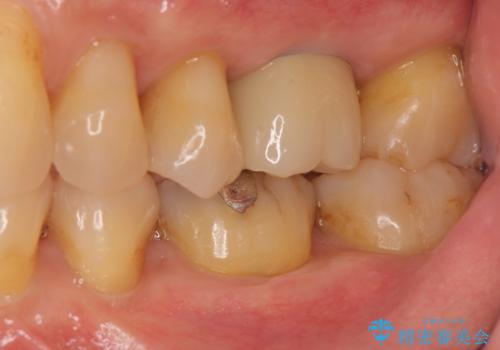

奥歯の欠損 インプラントによる咬合機能回復

- 奥歯を失い噛めないことの治療を希望され来院されました。

臨在する歯が虫歯もなく健全であるため、ブリッジではなくインプラントを用いた機能回復を計画します。

インプラントを用いることで、隣の歯を削ることなくしっかりと噛む機能を回復させることができます。